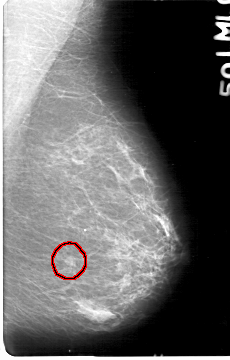

D_4047_1.RIGHT_MLO

LEFT_MLO LINES 5386 PIXELS_PER_LINE 3436 BITS_PER_PIXEL 12 RESOLUTION 43.5 OVERLAY

FILE: D_4047_1.LEFT_MLO.OVERLAY

TOTAL_ABNORMALITIES 1

ABNORMALITY 1

LESION_TYPE MASS SHAPE OVAL MARGINS OBSCURED

ASSESSMENT 0

SUBTLETY 4

PATHOLOGY BENIGN

TOTAL_OUTLINES 1

BOUNDARY